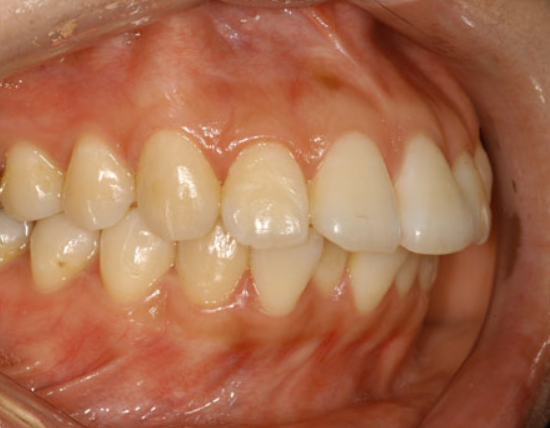

5. 입 안 치아 사진